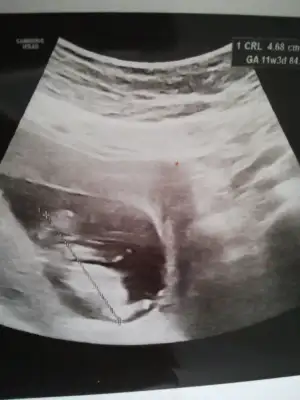

Kız gibi gibi diyorum net degil başka usg varsa tekrar tahmin ederimMerhaba bunlar da benim ultrason görüntülerim, yorumlar mısınız rica etsem. 11+3'deyiz![]()

Kız gibiMerhaba hanımlar, şimdi dr.dan geldim adete göre 10+6 ultrasona göre 11+6, banada cinsiyet tahmini yapar mısınız rica etsem?

Çok teşekkür ederim tüm ultrason görüntülerini paylaştım 10 gün sonra tekrar gideceğim inşallah doktorum da kız derKız gibi gibi diyorum net degil başka usg varsa tekrar tahmin ederim